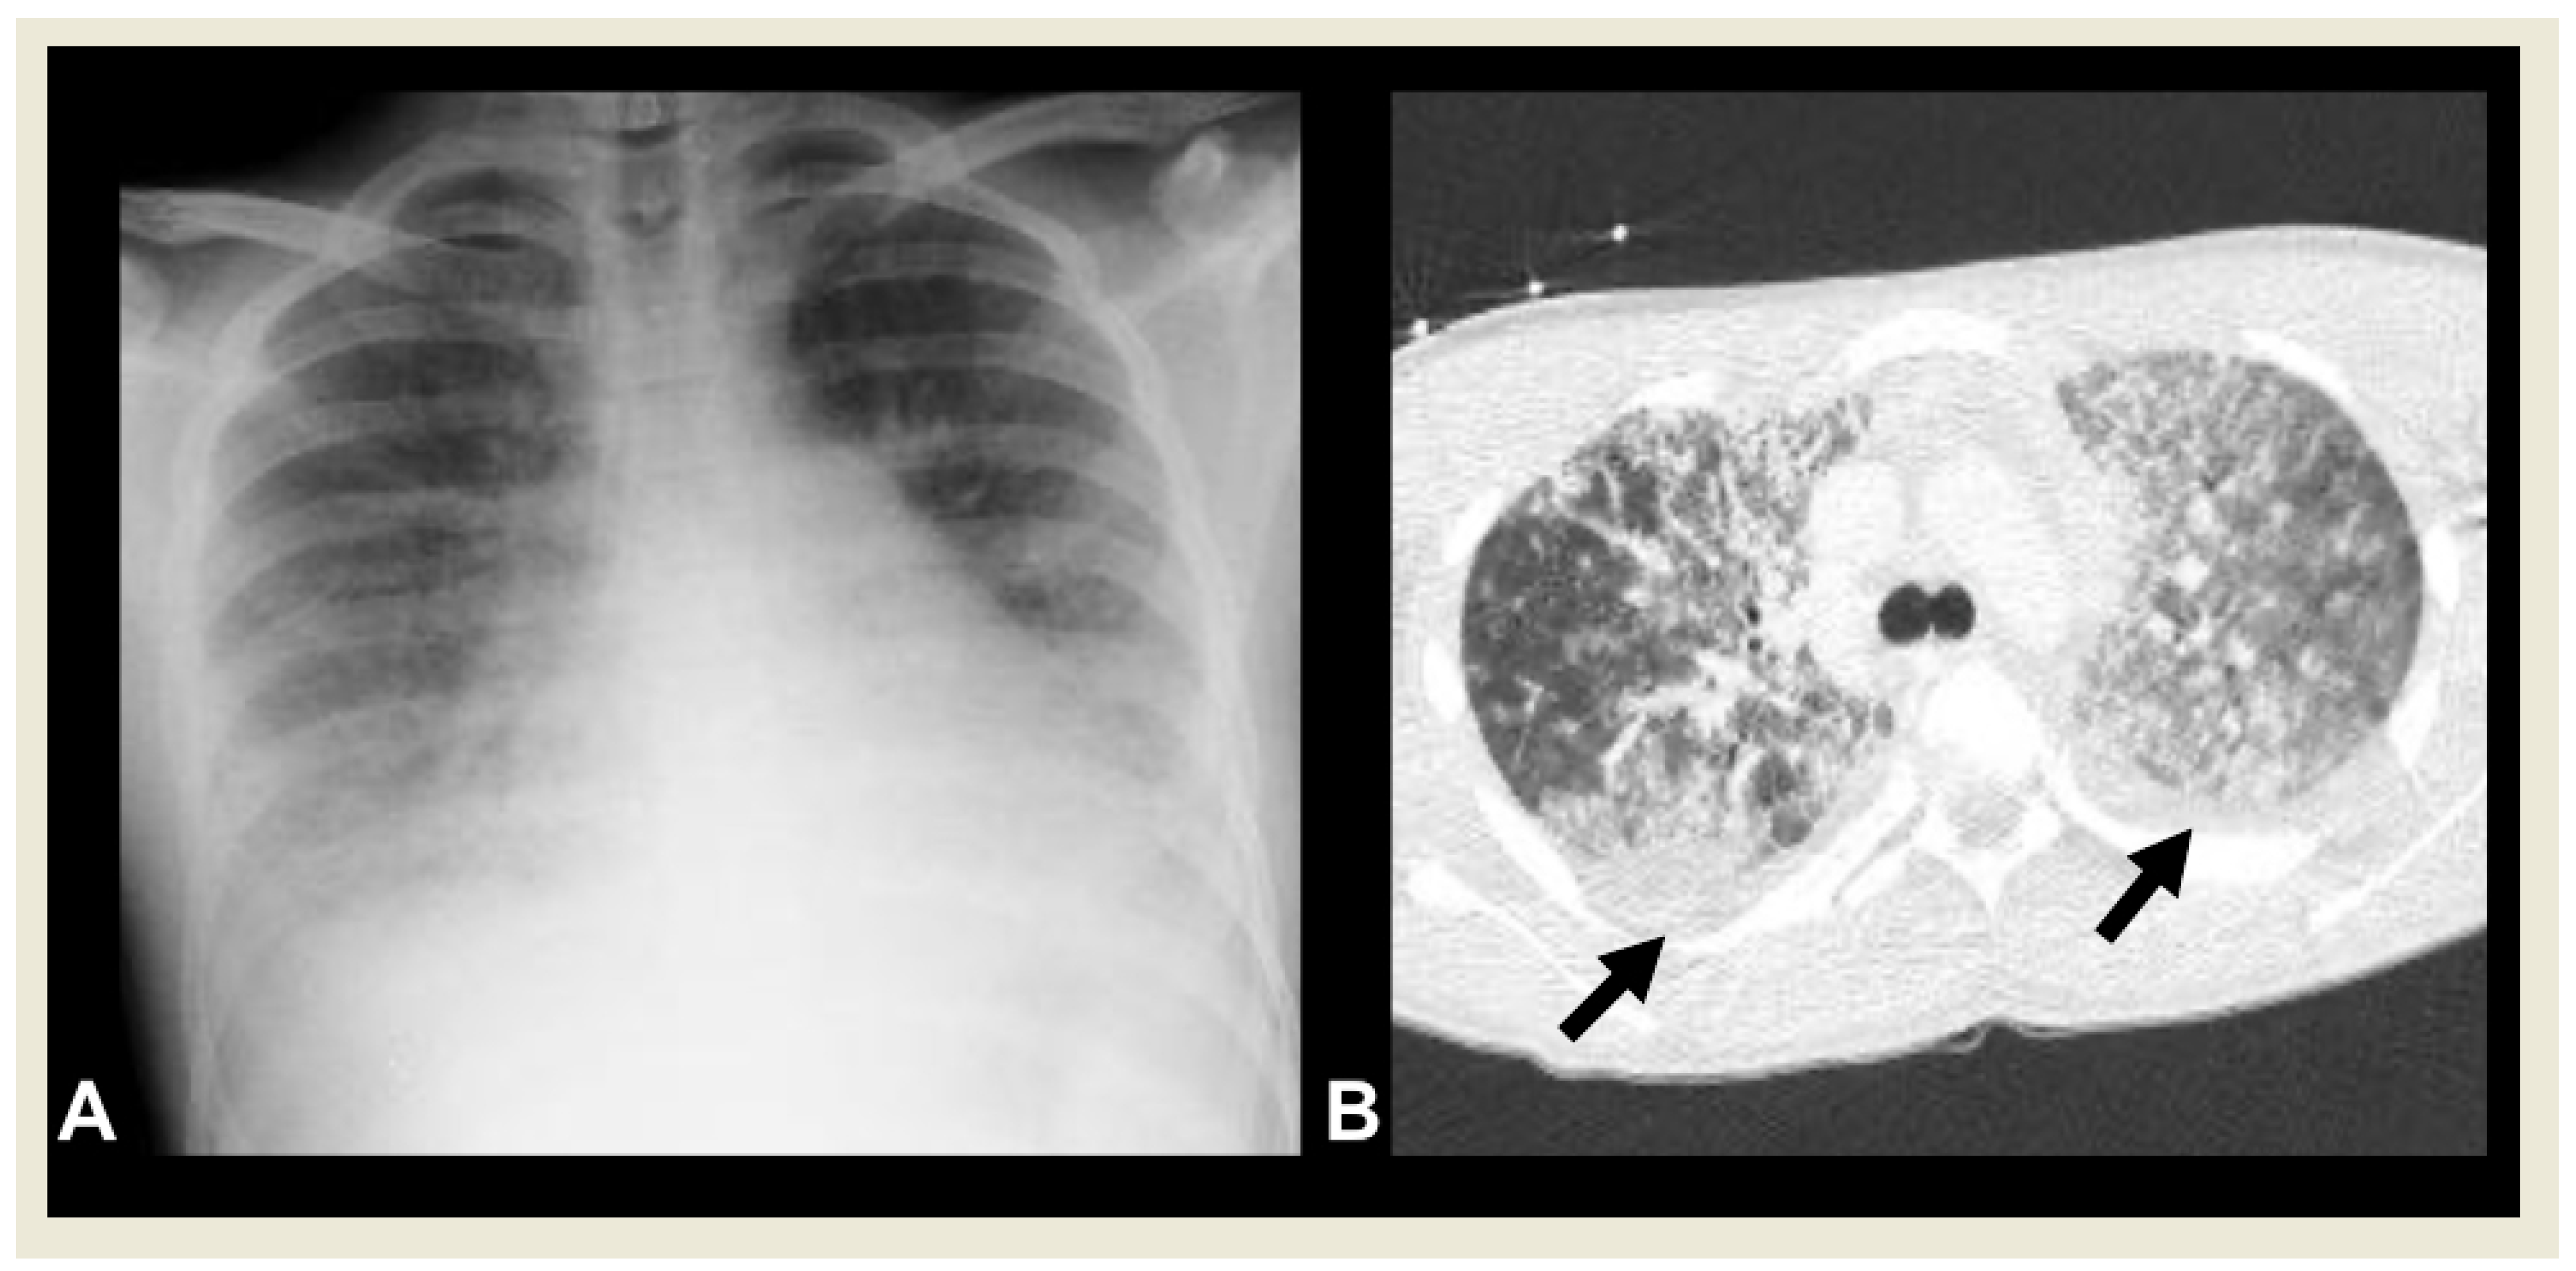

2.4.7. Pediatric Acute Respiratory Distress Syndrome (PARDS)